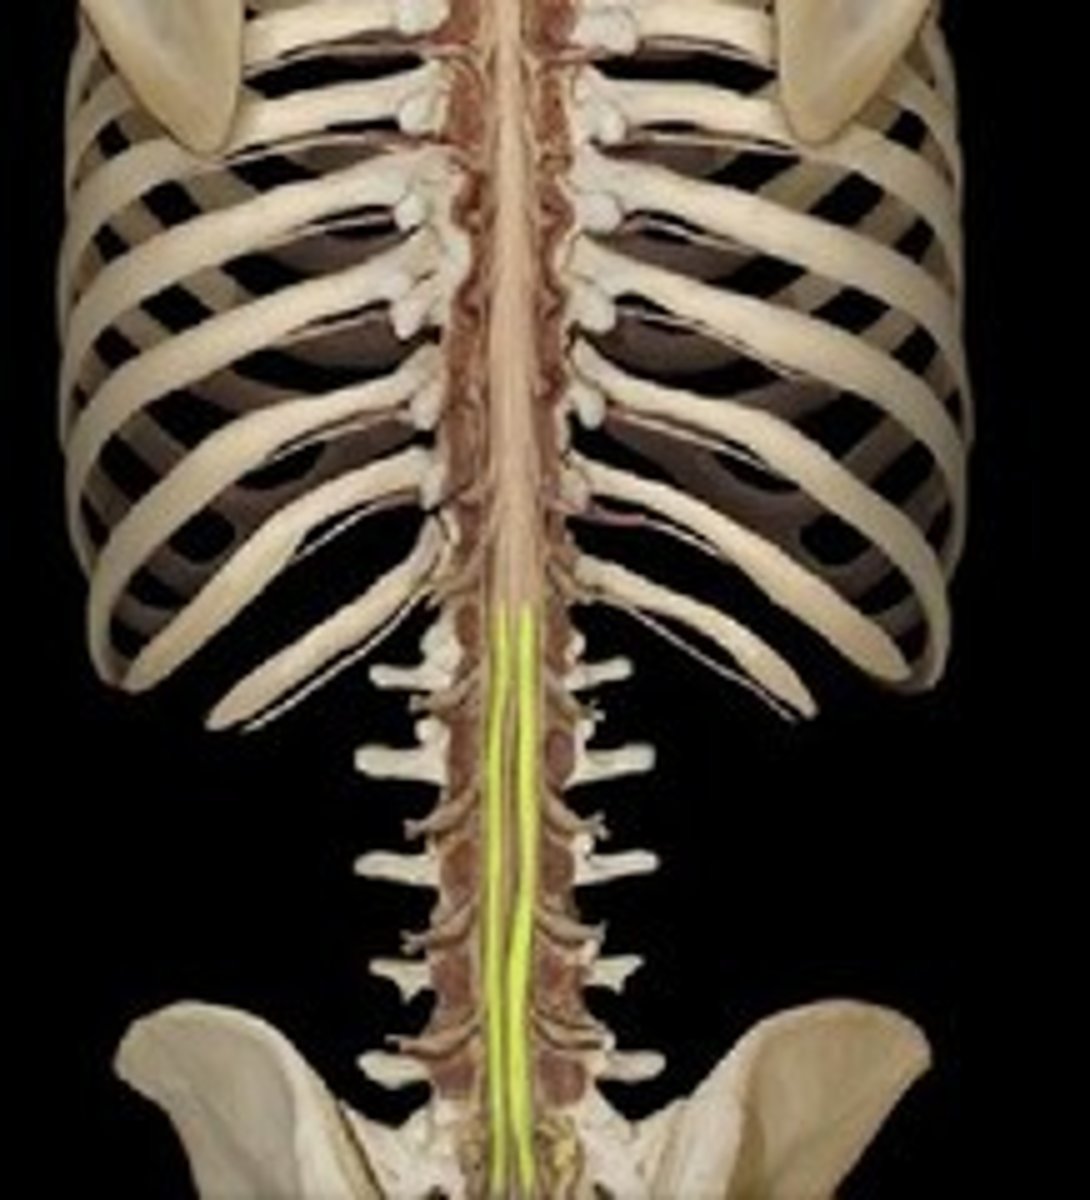

conus medullaris

cauda equina

dorsal root ganglion (spinal)